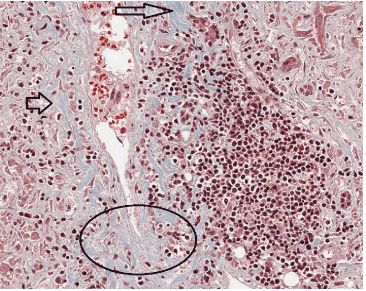

Her oncologist was concerned that there was hematogenous seeding of her epithelioid hemangiodendothelioma to the liver. Hepatitis antibodies, quantitative immunoglobulins, ceruloplasmin, ferritin, and acetaminophen level did not reveal an etiology of her liver function abnormalities. Anti-smooth muscle antibody (ASMA), liver-kidney-microsomal antibody (anti-LKM), antinuclear antibody (ANA), anti-mitochondrial antibody (AMA), and anti-soluble liver (anti-SLA) were nonreactive. Magnetic resonance cholangiopancreatography (MRCP) revealed nonspecific mild periportal edema (represented by arrows) and gallbladder wall thickening to 3.3 mm (with the upper limit of normal being 3mm) without obvious mass or biliary abnormality (Figure 1). After the initial negative workup, we proceeded to a liver biopsy. An intense lymphoplasmacytic portal infiltrate (encircled) was observed on the hematoxylin and eosin (H&E) stain (Figure 2). The trichome stain confirmed the diagnosis of autoimmune hepatitis as collagen stained a light blue (represented by arrows and a circle) suggesting a mild periportal fibrosis which is observed in all but the mildest cases of autoimmune hepatitis (Figure 3). Our patient’s hepatitis responded to a four month oral prednisone taper.

Figure 2. Lymphoplasmacytic portal infiltrate (encircled).